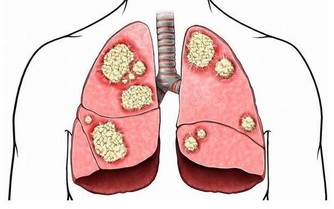

這個病名很專業,可能很多非血液科的醫生都沒聽到過。說直白點,就是患者的造血幹細胞惡性克隆,導致無效造血。白血病,我們通常稱之為血癌,骨髓增生異常綜合征其實也是一種血液腫瘤。這種病預後很差,有30%左右的患者會發展為白血病。

研究認為,苯是染髮劑中最基本的化學物質,對造血系統具有強烈毒性。染髮劑使用一個階段后,苯會沿頭髮浸入頭皮毛細血管,破壞造血系統,引起頭暈、乏力、皮下、內臟和腦出血,更加嚴重的是誘發癌症。近年來,醫學界常使用「染髮白血病」這個名詞,表明了染髮與白血病的關係。

染髮劑一般分為暫時性染髮劑、半持久性染髮劑和持久性(氧化型)染髮劑,絕大多數人使用的是持久性染髮劑。持久性染髮劑含有對苯二胺(PPD),這是目前使用最廣泛的著色劑成分。PPD是一種公認的致癌物質,流行病學調查顯示它可以增加患膀胱癌的風險,特別是黑色染髮劑,含PPD的量相對較高。

美國和加拿大一項研究調查了766名成人白血病患者和623名沒有得過白血病的健康人,與沒有使用染髮劑的人比較,使用持久性染髮劑和半持久性染髮劑者患急性白血病的危險性較高。